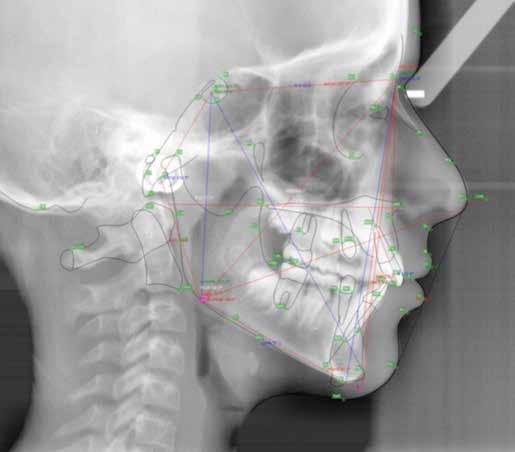

Alla risoluzione della malocclusione scheletrica e dentale si associa un netto recupero della postura con conseguente miglioramento della curva cervicale, come è possibile verificare nella teleradiografia finale.

47 46 ESTETICA FUNZIONE POSTURA Valori cefalometrici a 10 anni : ANB ANB 2.70 Posizione del Mascellare SNA 78,70 Posizione della Mandibola SNB 76.0 Angolo Articolare SArGo 142,76 Angolo Goniaco ArGoMe 125,73 Angolo incisivo inf^Corpo madibolare IiMand 92,00 Angolo incisivo Sup^Base Cranica Ant. IsCran 96,00 Angolo Interincisivo II 130,0 53 _ Esame Cefalometrico a dieci anni. 54 _ Tabella dei valori cefalometrici a dieci anni. 55 _ Ortopantomografia di controllo a dieci anni. 56 _ Teleradiografia di controllo con evidente stabilità del caso dal punto di vista scheletrico/posturale.

> La documentazione a dieci anni mostra la stabilità del caso e

come l’occlusione, elastodonticamente individuata, costituisca anche la contenzione stessa. La paziente ha smesso di

Considerazioni

indossare l’apparecchio elastodontico dopo due anni e mezzo di terapia, conservando parametri occlusali e posturali in rapporto corretto tra loro.

Nel 2019 si è provveduto all’avulsione chirurgica degli elementi dentari 18, 28, 38 e 48.